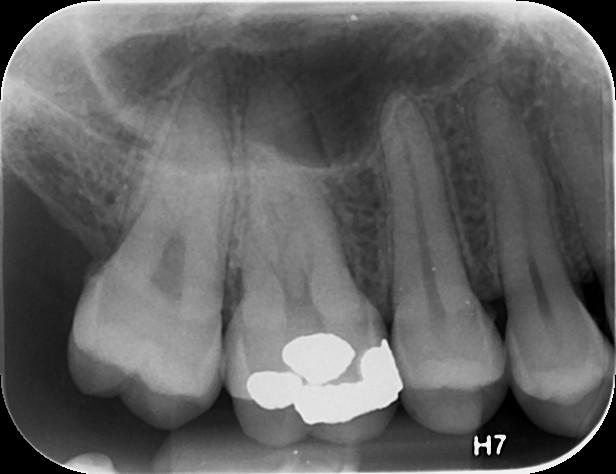

Η οπισθοφατνιακή ακτινογραφία λαμβάνεται με την τοποθέτηση του ακτινογραφικού πλακιδίου εσωτερικά των δοντιών (προς την πλευρά της γλώσσας ή του ουρανίσκου) και παράλληλα με αυτά. Χρησιμοποιείται ειδικός συγκρατητήρας του φιλμ, τον οποίο δαγκώνει ο εξεταζόμενος. Με αυτή απεικονίζονται ένα ή περισσότερα δόντια (τόσο η μύλη, όσο και η ρίζα αυτών), καθώς και τμήμα του φατνιακού οστού που περιβάλλει τις ρίζες των δοντιών. Αποτελεί την πιο απλή οδοντιατρική ακτινογραφική απεικόνιση. Χρησιμοποιούνται τρία μεγέθη φιλμ ή πλακιδίου ανάλογα με την περιοχή που θέλουμε να απεικονιστεί, το μέγεθος του στόματος του εξεταζόμενου και την ηλικία του. Η λήψη της είναι γρήγορη (διαρκεί λίγα δευτερόλεπτα) και ανώδυνη.

• την ανίχνευση οδοντικών τερηδόνων, τον καθορισμό της έκτασης και του βάθους τους και της σχέσης τους με τον πολφό του δοντιού

• τη μελέτη των ριζών των δοντιών (αριθμός, μορφολογία και πιθανή κάμψη αυτών, ύπαρξη απορρόφησης ή κατάγματος)

• τη μελέτη του αριθμού, της μορφολογίας, του εύρους και της πορείας των ριζικών σωλήνων εντός των ριζών

• τη μελέτη των σκληρών ιστών του περιοδοντίου, δηλαδή του φατνιακού οστού που περιβάλλει και στηρίζει το δόντι και του περιοδοντικού συνδέσμου. Σε περίπτωση περιοδοντικής νόσου, καθορίζεται η εντόπιση, ο βαθμός και η φύση (οριζόντια, γωνιώδης) της απορρόφησης του φατνιακού οστού

• τη μελέτη του φατνιακού οστού της περιακρορριζικής περιοχής του δοντιού για ύπαρξη παθολογικών εξεργασιών (απόστημα, κοκκίωμα, κύστη κ.λ.π.)

• την ανίχνευση κατάγματος των δοντιών.